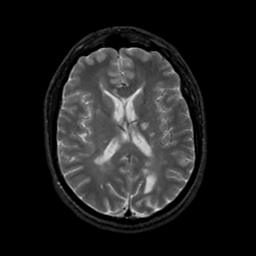

MR Study #19, August 25, 1991 -- Slice #29